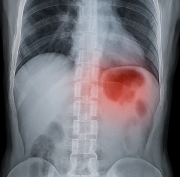

혈뇨가 나오는 이유 – 종양(방광암, 신장암 등)

혈뇨가 나오는 이유 중 가장 우려되는 것은 종양입니다. 방광암, 신장암, 요관암 등은 혈뇨를 초기 신호로 보이는 경우가 많습니다. 특히 통증이 없는 혈뇨가 반복적으로 나타난다면 반드시 암 검진이 필요합니다. 암으로 인한 혈뇨는 조기 발견이 예후를 좌우합니다.